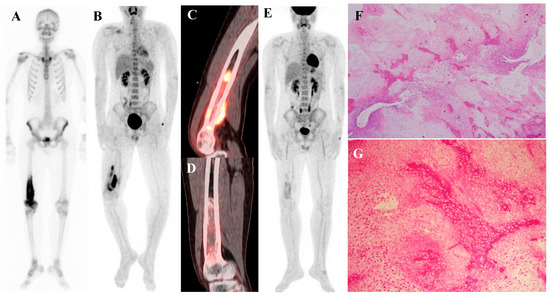

Current Position of Nuclear Medicine Imaging in Primary Bone Tumors

Primary bone tumors encompass a heterogeneous spectrum ranging from benign entities to highly aggressive sarcomas. This review aims to summarize the current role and future perspectives of nuclear medicine in the diagnosis, staging, and management of primary bone tumors. Accurate diagnosis and staging [...] Read more.

Primary bone tumors encompass a heterogeneous spectrum ranging from benign entities to highly aggressive sarcomas. This review aims to summarize the current role and future perspectives of nuclear medicine in the diagnosis, staging, and management of primary bone tumors. Accurate diagnosis and staging are critical yet challenging due to histologic heterogeneity and overlapping imaging features. While radiographs, computed tomography (CT), and magnetic resonance imaging (MRI) remain essential, nuclear medicine provides a complementary functional perspective by assessing bone turnover, vascularity, and glucose metabolism. Bone scintigraphy is highly sensitive for skeletal lesions and useful for detecting skip lesions or multifocal disease, although its specificity is limited. Hybrid single-photon emission computed tomography (SPECT)/CT enhances diagnostic confidence through precise anatomic localization and quantitation. [18F]fluorodeoxyglucose ([18F]FDG) positron emission tomography (PET)/CT, by directly visualizing tumor metabolism, has become a cornerstone in osteosarcoma and Ewing sarcoma management, demonstrating superiority over bone scintigraphy for detecting skeletal metastases. In chondrosarcoma, [18F]FDG uptake correlates with histologic grade, although overlap with benign cartilage tumors complicates interpretation. Future directions include the integration of quantitative SPECT, artificial intelligence, and novel tracers such as [18F]sodium fluoride and [68Ga]Ga-fibroblast activation protein inhibitor (FAPI). Collectively, nuclear medicine imaging is becoming a key element in musculoskeletal oncology, offering unique biological insights that complement anatomic imaging and contribute to improved patient management. Full article

Show Figures

Figure 1